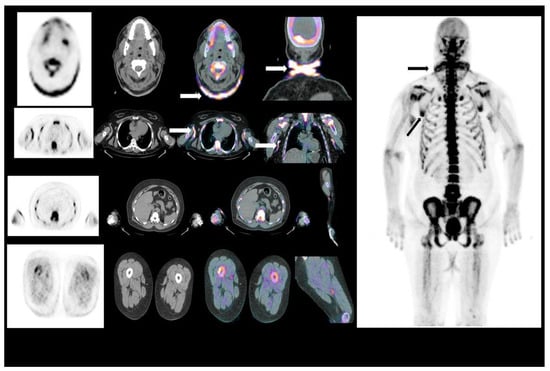

Cutaneous and Vascular Deposits of 18F-NaF by PET/CT in the Follow-Up of Patients with Pseudoxanthoma Elasticum

3.2. Arterial Wall Uptake of 18F-NaF

3.3. Skin Uptake of 18F-NaF